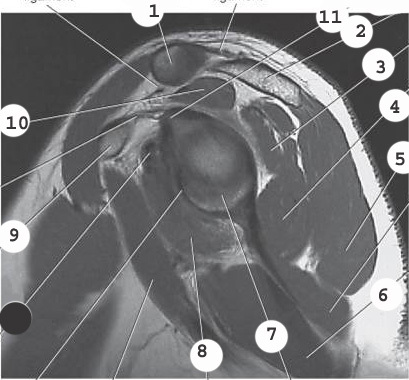

1

labrum

3

infraspinatus muscle

4

deltoid

2

acromion

teres minor muscle

5

8

subscapularis muscle

10

supraspinatus muscle